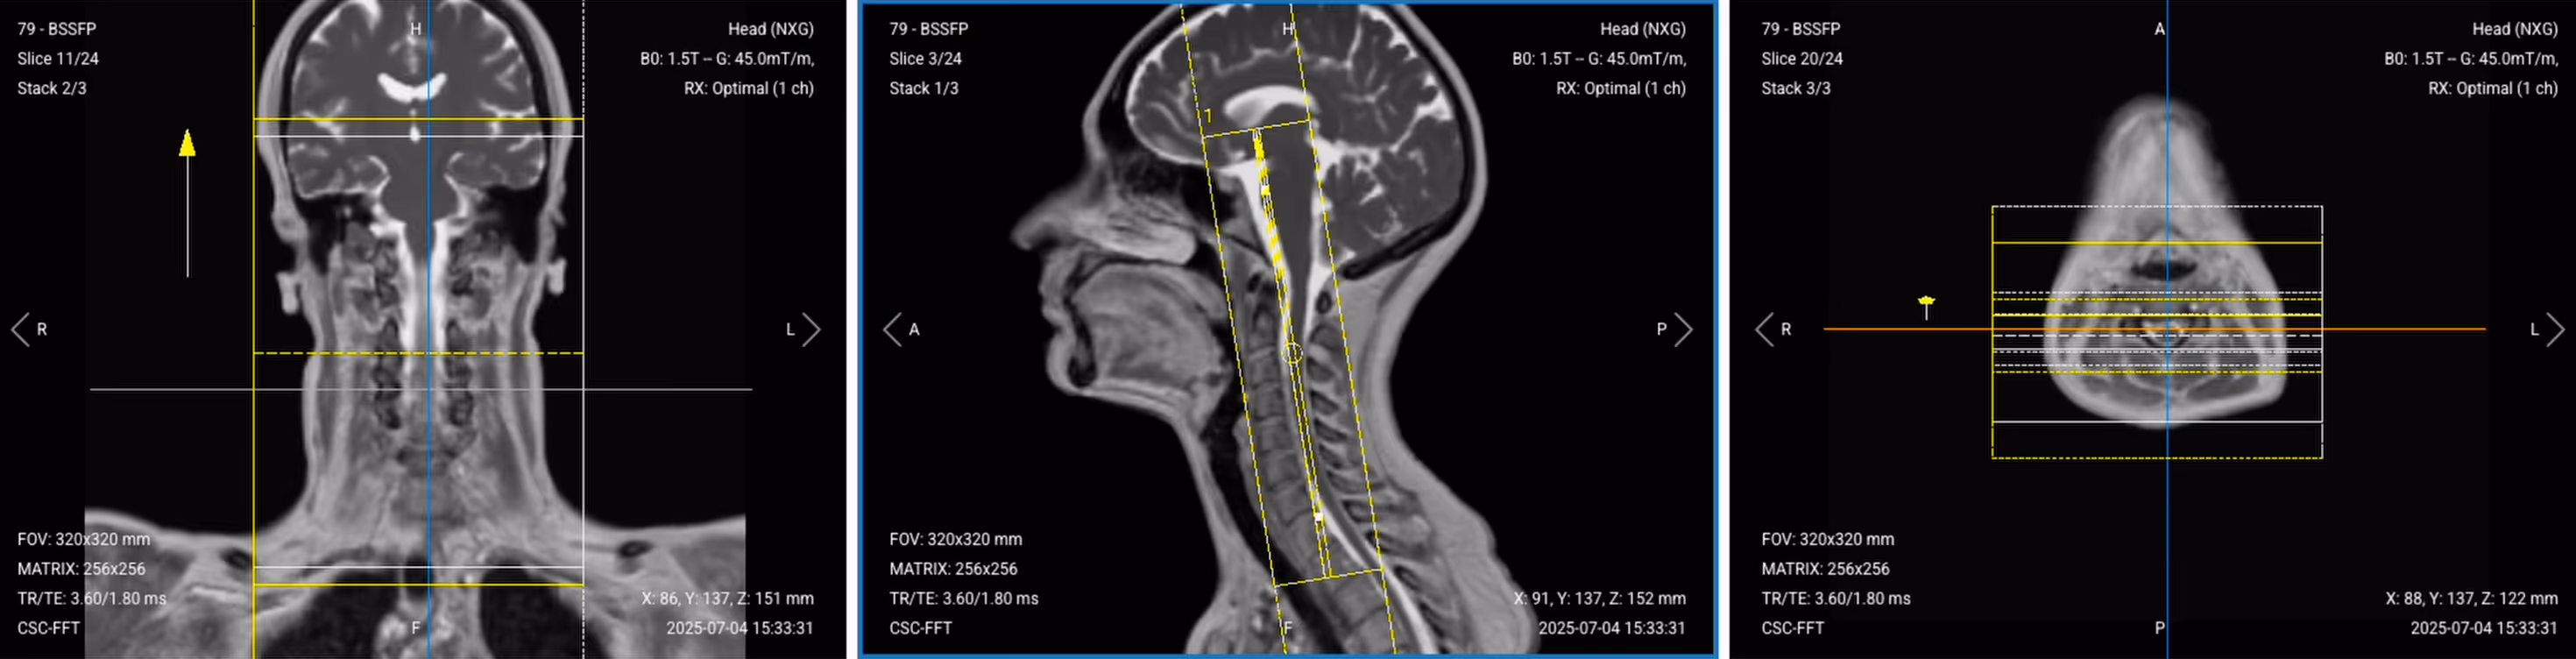

Correct Setup of Localizer Images for Cervical Spine MRI:

Correct setup of localizer images for Cervical Spine MRI

3. Capture the Initial Localizer Images

Before we can perform any MRI protocol, we must always capture initial localizer images of the patient. These images act as a guide for planning the detailed scans we will perform next.

We should always capture localizers in three planes:

1. Axial

2. Sagittal

3. Coronal

Once acquired, upload the initial localizer images into the three viewports.

Then, scroll through each of the image stacks to locate a central slice that clearly shows the anatomy of the cervical spine.